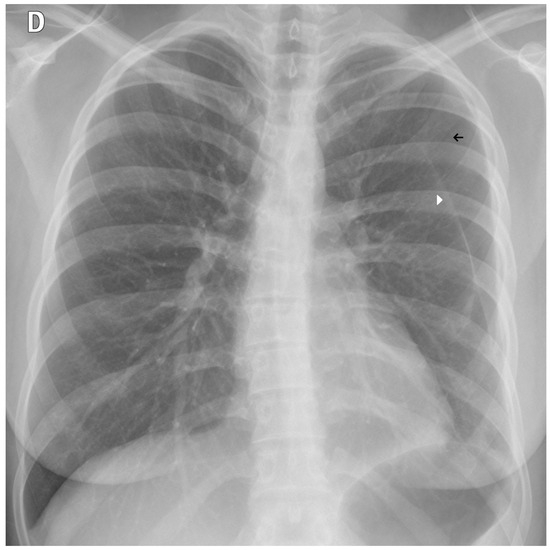

Figure 9. A false negative example of a small, missed nodule (black arrow).

Figure 10. A false negative example of an alveolar opacity (black arrow).

3.3. Error Analysis

An analysis of the algorithm’s false negatives revealed a nuanced performance profile, where a specific miss did not always equate to a complete system failure. Across the board, a substantial number of cases with a false negative for a particular pathology were nevertheless correctly identified as abnormal by the general “yes-finding” classifier or had other co-occurring true positive pathologies. For example, out of 38 false negatives for opacity, the algorithm correctly identified the exam as abnormal in 25 cases. In many instances of a missed finding, the algorithm successfully detected other pathologies within the same study. Misclassification was another notable source of error, where an existing pathology was detected but incorrectly labeled, such as opacities being predicted as masses or nodules (Figure 4). Radiologist review of these false-negative cases frequently noted findings that were “subtle,” “small,” “doubtful,” “seen on lateral image only,” or “non-specific.” In other cases, the algorithm correctly identified a more critical finding, like a large pleural effusion, while missing a secondary, less significant pathology (Figure 3). Figure 9, Figure 10 and Figure 11 illustrate false negative cases for opacity, pneumothorax, and nodule, respectively. This highlights the inherent limitations and inevitable failures of this kind of system.